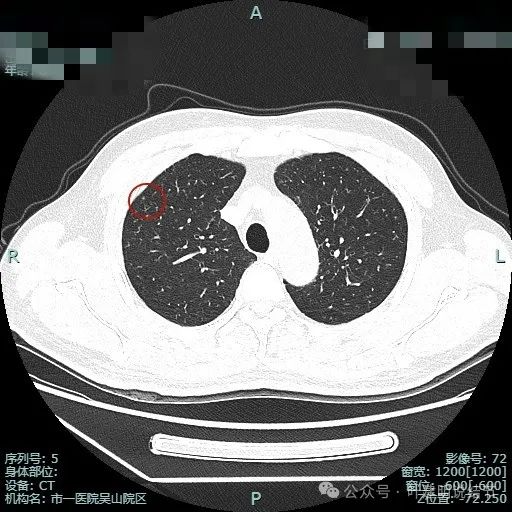

先来看两肺多发结节的总体情况:

病灶3:右上叶点状偏高密度微小结节,只有1毫米许,无法定性,但增殖灶的可能性大点,因为密度感觉稍显高。

病灶4:左上叶点状高密度结节,良性可能性较大。

病灶5:右上叶前段血管旁微小磨玻璃结节,轮廓较清,与血管挨得近,考虑是肺泡上皮增生或不典型增生可能性大。

病灶6:右上叶后段磨玻璃结节,有浅分叶征,结合前面图上有血管穿行,考虑是肿瘤范畴的,以微浸润性腺癌或浸润性腺癌贴壁为主型可能性大。

病灶7:左上叶胸膜下微小不足1毫米点状高密度,无法定性,但良性可能性大,因为密度显得较高;

病灶8:距离胸膜约1.5厘米许微小磨玻璃结节,大概1-2毫米之间,轮廓较清,以肺泡上皮增生可能性较大;

病灶9:左上叶胸膜下微小结节,密度不如病灶7高,又不如病灶8大,无法确定性质,但必能随访。

病灶10:右上叶胸膜下微小结节,表面不平,密度也非实性,显得形态不太规则,考虑良性或肿瘤范畴的原位癌或微浸润性腺癌均可能,但太小了,如果只有此灶只需随访。

病灶11:右肺实性结节,边缘略模糊,缺乏膨胀感,考虑良性可能性大些。

病灶12:右下叶微小结节,点状,密度较高,良性增殖灶可能性大。

病灶13:左上叶舌段磨玻璃结节,但呈长条状,贴着胸膜,纤维条索可能性稍大,但由于密度不够高,也无法完全除外肿瘤范畴的肺泡上皮增生或不典型增生,但必能随访。

病灶14:左上叶微小结节,密度较高,但未钙化,考虑增殖灶可能性大。